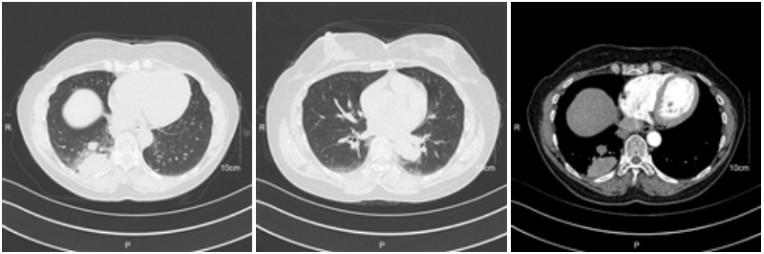

患者肺部CT如图1所示,两肺下叶散在团片影,考虑炎性病变可能大。实验室检查结果如表1所示。由于长期使用免疫抑制剂,患者处于免疫功能低下状态,血清隐球菌荚膜抗原阳性是诊断隐球菌病的关键。

图片

1  患者肺部CT

患者入院后,在诊断不明确时先予以莫西沙星经验性抗感染治疗。在住院第3天获得明确病因,加用氟康唑进行针对性抗感染治疗。治疗1周后,患者未出现不良反应,且病情恢复良好,于是同意带药出院。两个月后患者回我院复查肺部CT,阴影较之前明显缩小吸收(图3)

图3  患者复查CT图像